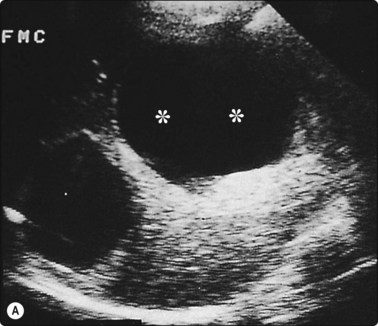

Fine needle biopsies of liver lesions, including hydatids and hemangiomata, are safe provided the needle passes through normal liver tissue to act as a seal (Fig. 3.10).

image image

Fig. 3.10 Aspiration biopsy of hydatid disease without complication

(A) Two clearly defined anechoic cysts within the liver. The more anterior cyst (**) was completely aspirated without complication. (B) Five months later the patient was rescanned and multiple loculi within the cyst provided the diagnosis of hydatid disease. This was confirmed at surgery.